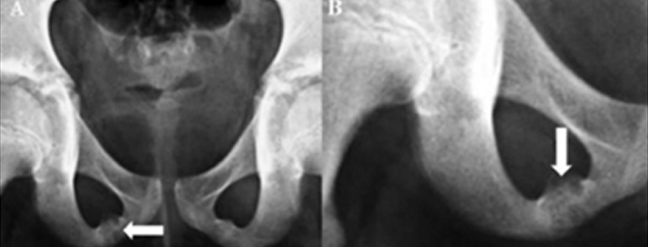

Κατάγματα ηβοϊσχιακών κλάδων

Μετά από πτώση παρουσιάζεται πόνος χαμηλά εμπρός στην περιοχή του ενός ισχίου, που επιτείνεται στη βάδιση.

– Οστεοπόρωση

– Καθυστερημένη πώρωση